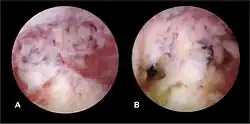

The history of a pregnancy event followed by a D&C leading to secondary amenorrhea or hypomenorrhea is typical. Hysteroscopy is the gold standard for diagnosis.[18] Imaging by sonohysterography or hysterosalpingography will reveal the extent of the scar formation. Ultrasound is not a reliable method of diagnosing Asherman's Syndrome. Hormone studies show normal levels consistent with reproductive function.

Fertility may sometimes be restored by the removal of adhesions, depending on the severity of the initial trauma and other individual patient factors. Operative hysteroscopy is used for visual inspection of the uterine cavity during adhesion dissection (adhesiolysis). However, hysteroscopy is yet to become a routine gynaecological procedure and only 15% of US gynecologists perform office hysteroscopy.[32] Adhesion dissection can be technically difficult and must be performed with care to not create new scars and further exacerbate the condition. In more severe cases, adjunctive measures such as laparoscopy are used in conjunction with hysteroscopy as a protective measure against uterine perforation. Microscissors are usually used to cut adhesions. Electrocauterization is not recommended.[33]